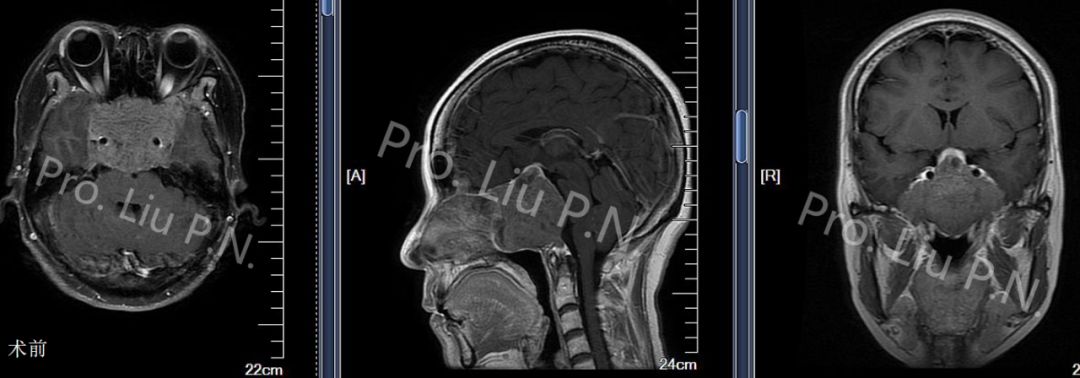

六、扩大经蝶窦入路手术案例

--侵袭性垂体瘤

![]()